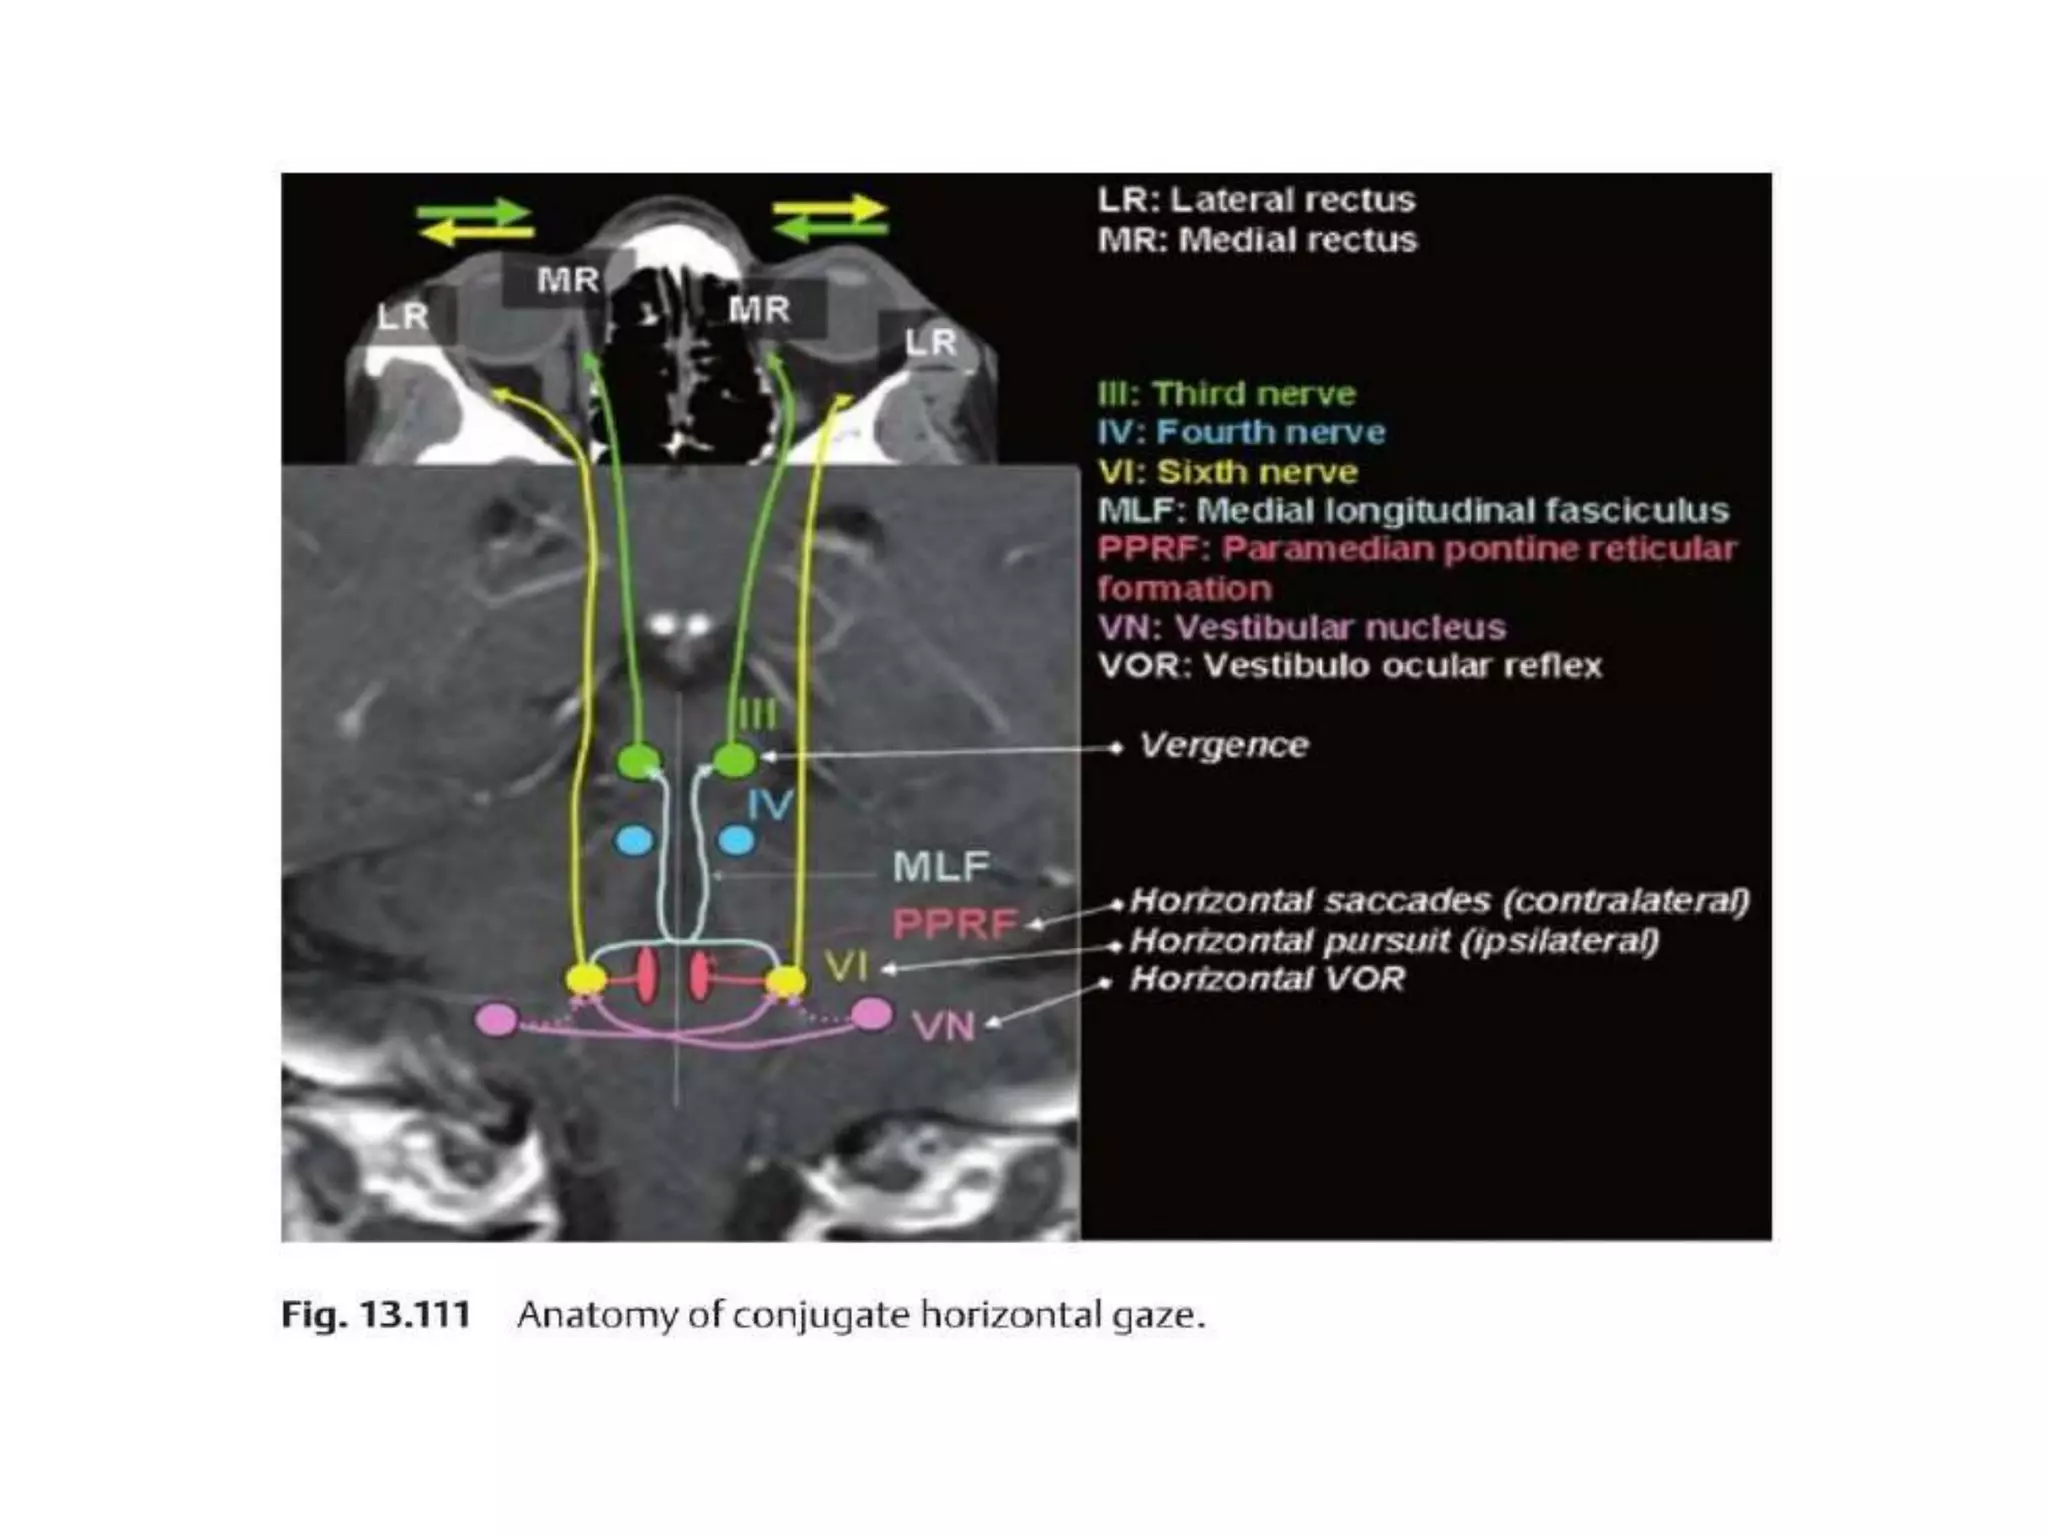

Horizontal gaze paresis

• Lesion of 6th n. nucleus

– Loss of ipsilat. Voluntary and reflexive conjugate

movement

Internuclear ophthalmoplegia

• Lesion of MLF

– Ipsilesional deficit of adduction

– Nystagmus

– Convergence may overcome adduction deficit

Horizontal gaze paresis •Lesion of 6th n. nucleus – Loss of ipsilat. Voluntary and reflexive conjugate movement – Ipsilat. Facial weakness

Internuclear ophthalmoplegia • Lesionof MLF – Ipsilesional deficit of adduction – Nystagmus – Convergence may overcome adduction deficit